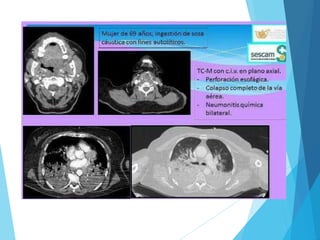

 Estudios radiológicos: - Fase aguda: Rx simple de tórax

 TAC con contraste oral (método mas sensible para

detectar una perforación incipiente).